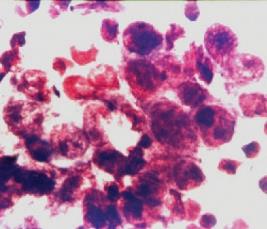

A herpesvírus-fertőzések diagnózisa. A legtöbb eset diagnózisa egyértelműen klinikai, de kimutatható kenetben, tenyésztéssel, csirkeembrió chorioalantois hártyáján, elektronmikroszkóppal és direkt immunfluoreszcenciával (6.4. ábra6.6. ábra).

6.4. ábra. Herpeses betegtől vett kenet May–Grünwald–Giemsa-festése